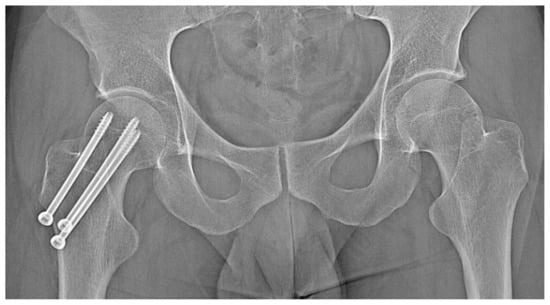

3.2. Case 2: Example of an Incorrect Therapeutic Path of OO